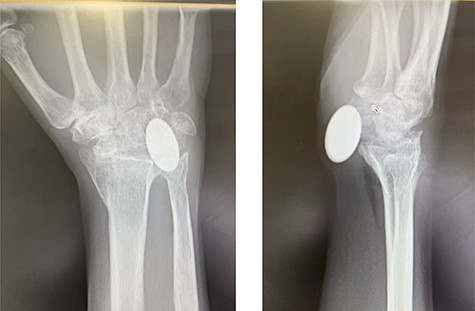

A 50-year-old, right-hand-dominant woman, presented with a history of stiffness and pain affecting her right wrist, associated with a history of increasing swelling on its palmar aspect. She had been treated for post-traumatic arthritis of the same wrist 7 months earlier by arthroplasty with a Pyrocarbon Amandys implant; she also reported gradual onset of tingling sensations in her ring finger. She had an initial uneventful recovery but developed clinical symptoms of carpal tunnel syndrome 2 months later, with paresthesia in the right thumb and index finger radiating to the forearm, which was worse at night. A diagnosis of carpal tunnel syndrome was confirmed by nerve conduction studies. Post-operative radiograph at this time showed the pyrocarbon implant in an adequate position (Fig. 1).

X-rays of the right hand showed palmar displacement of the pyrocarbon implant.